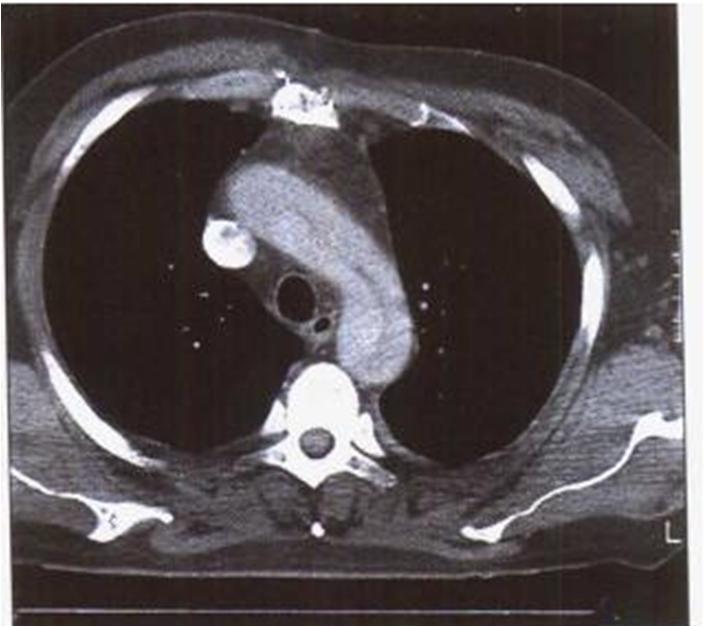

(2)主动脉夹层CT可见: 主动脉腔内见一X-线可穿透的线是内膜夹层

胸主动脉增强CT造影红箭头示主动脉弓破口处:

在MPR, CPR图象中,主动脉夹层的真假腔显示不同密度,真腔明显强化,真腔小而假腔大,真腔明显受压变窄,可见低密度血栓。